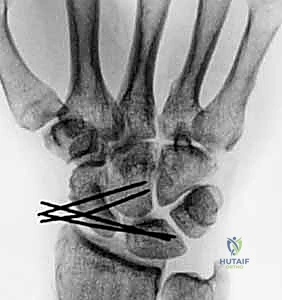

- Technique (Scapholunate Pinning):

- Reduction: First, we must achieve an anatomical reduction of the scapholunate interval. This is often accomplished by direct manual pressure on the scaphoid tubercle and lunate, or by using a small probe to manipulate the bones into alignment. We'll confirm reduction with fluoroscopy.

- Pin Placement: We typically use two 0.045-inch Kirschner wires. The first K-wire is usually inserted from the scaphoid, across the scapholunate joint, into the lunate. The entry point on the scaphoid is typically on its dorsal-radial aspect.

- Fluoroscopic Guidance: This step is absolutely critical. We'll use the mini C-arm to guide the K-wire placement. We need to ensure the wire is:

- Intra-articular: Crossing the scapholunate joint without violating the radioscaphoid or capitolunate joint.

- Central in the bones: Avoiding the edges to prevent breakage and maximize purchase.

- Parallel: The two wires should be parallel to each other, approximately 2-3 mm apart.

- Adequate Length: Sufficiently long to engage both the scaphoid and lunate without protruding excessively.

- Second Pin: A second K-wire is placed in a similar fashion for rotational stability.

- Pin Bending and Capping: Once satisfied with the position on fluoroscopy, the K-wires are cut and bent outside the skin, then capped to prevent migration and skin irritation.

FIG 5 • A. Percutaneous pinning of the scapholunate joint using two K-wires.

FIG 5 • B. Fluoroscopic image confirming satisfactory K-wire placement.